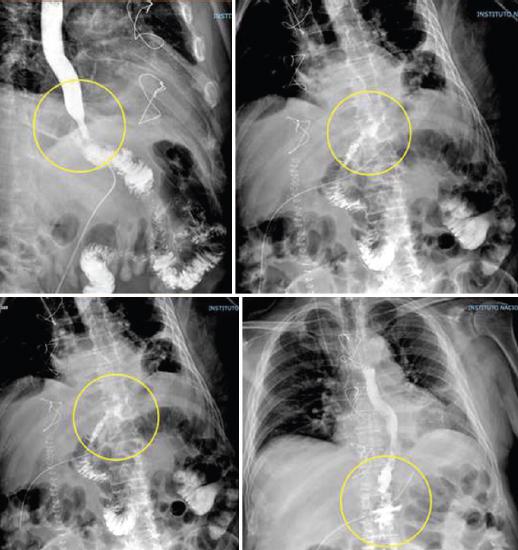

Concerning the diagnostic approach of EJAL, some authors have proposed the performance of contrast-enhanced esophagogram previous to start oral feedings in their patients33,34 (Fig. 1).

Figure 1 Contrast-enhanced esophagogram performed 4 days after total gastrectomy showing evidence of EJAL (yellow circle).

However, further evidence has demonstrated that this practice has a low diagnostic yield and should not be done on a regular basis35. On a study performed in our center, routine contrast enhanced esophagogram revealed to have a sensitivity of 86%, specificity 100%, positive predictive value 100%, and negative predictive value of 86% for detection of EJAL36.